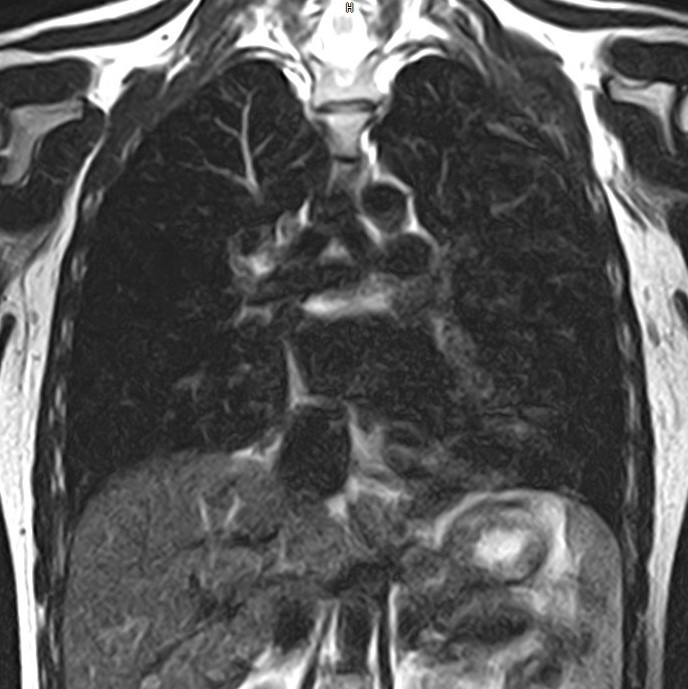

МРТ

Данный метод из всего списка является самым инновационным и современным. Благодаря своему принципу работы, МРТ дает четкую визуализацию с высоким разрешением. Такое исследование, в рамках органов грудной клетки, используется для исследования органов средостения. К сожалению, такое исследование не подходит для визуализации мельчайших очагов поражения в легочной ткани. Но стоит отметить, что существенным плюсом является отсутствие лучевой нагрузки, а вот существенным минусом со стороны пациента являются дороговизна исследования, длительность проведения исследования, а также наличие ряда относительных и абсолютных противопоказаний.